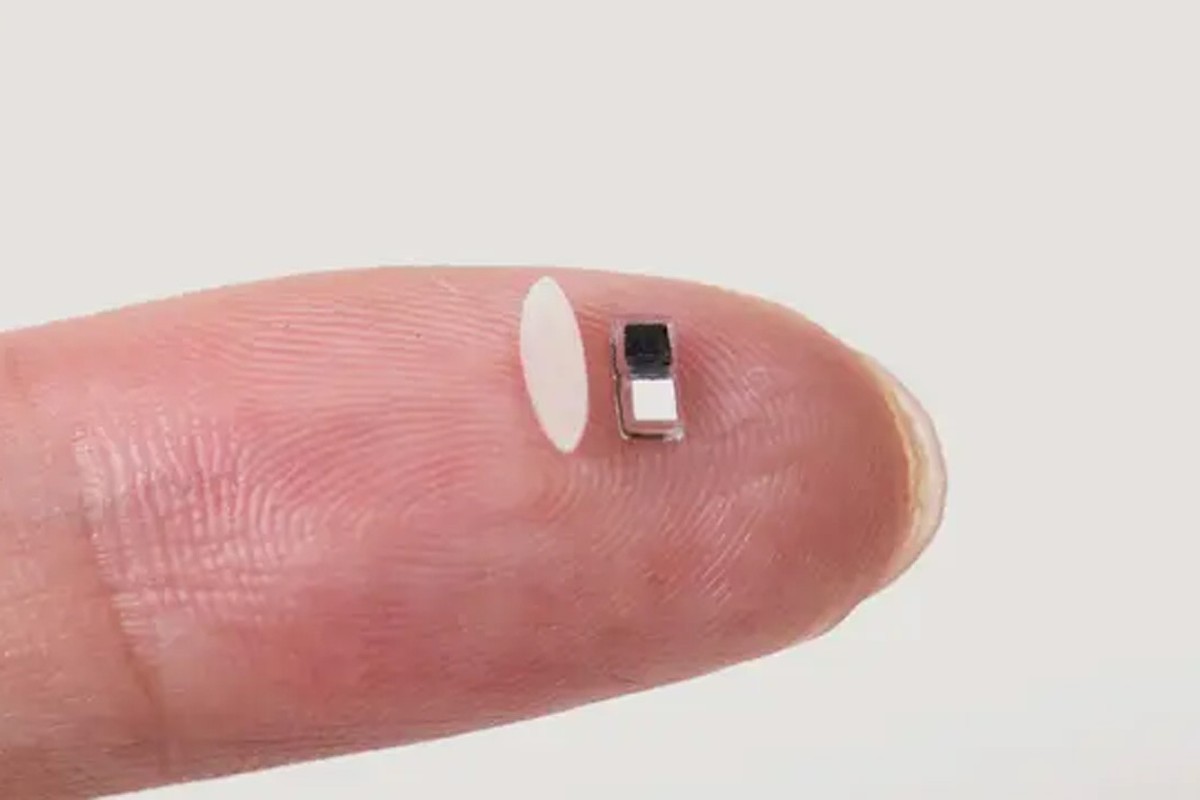

Stworzyli najmniejszy rozrusznik serca na świecie. To przełom w medycynie